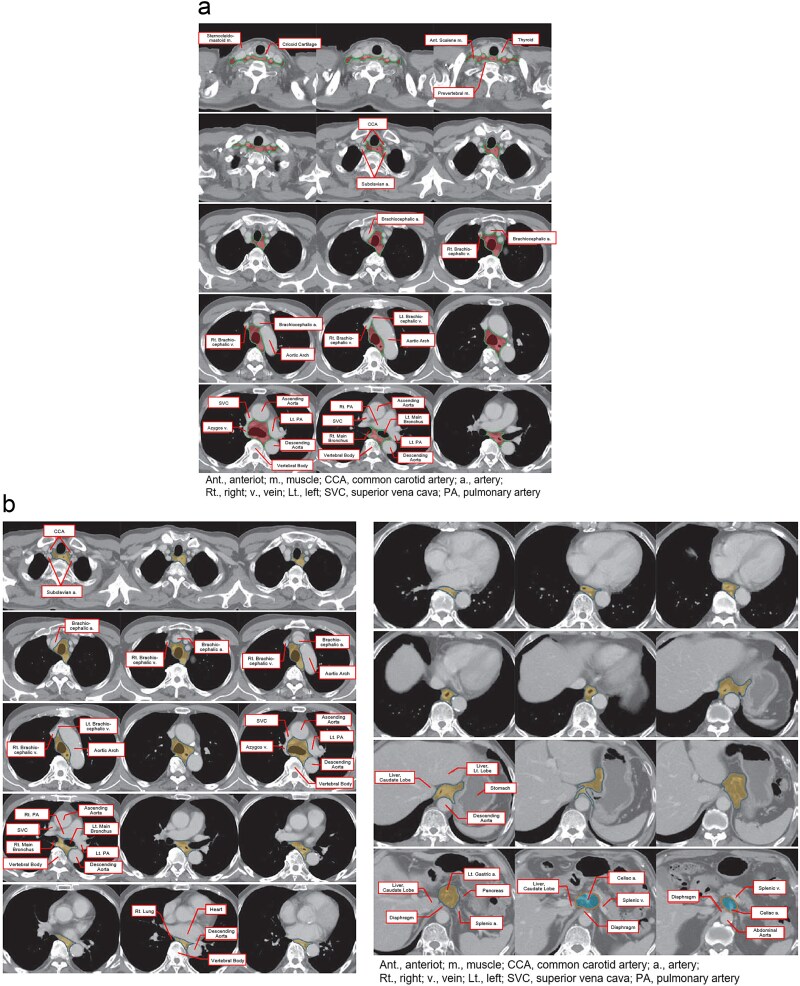

日本放射肿瘤学学会(JASTRO)放射治疗计划指南自2004年第一版出版以来,每四年修订一次,以纳入最新发现。这篇综述介绍了2024年JASTRO食管癌放疗计划指南的英文版本。关于食管癌的治疗,在过去的4年里出现了各种新的发现,导致2020年版的重大更新,特别是在以下六个方面:(i)浅表癌适应症的更多细节,(ii)日本局部晚期病例新辅助化疗和放化疗的临床试验结果(JCOG1109), (iii)预防性淋巴结照射的更新参考文献,(iv) IMRT的更新,(v)根据食管癌治疗指南第5版的修订,以及(vi)在同期化疗方案中增加FOLFOX。

The Japanese Society for Radiation Oncology (JASTRO) Guidelines for Radiotherapy Treatment Planning have been revised every four years to incorporate the latest findings since the publication of the first edition in 2004. This is a review which presents the 2024 JASTRO Guidelines for radiotherapy treatment planning for esophageal cancer in English. Regarding the treatment of esophageal cancer, various new findings have emerged over the past 4 years, leading to significant updates in the 2020 edition, particularly in the following six areas: (i) additional details on indications for superficial cancer, (ii) inclusion of clinical trial results (JCOG1109) for neoadjuvant chemotherapy and chemoradiotherapy in locally advanced cases in Japan, (iii) updated references on prophylactic lymph node irradiation, (iv) updates on IMRT, (v) revisions in accordance with the 5th edition of the Esophageal Cancer Treatment Guidelines, and (vi) additions of FOLFOX to concurrent chemotherapy regimens.